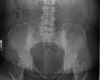

X-ray : 장골치밀화골염(Osteitis condensans ilii)

천장관절의 장골면에 삼각형(triangular)의 골경화가 주로 양측성으로 발생하며 간혹 일측성인 경우도 있습니다.